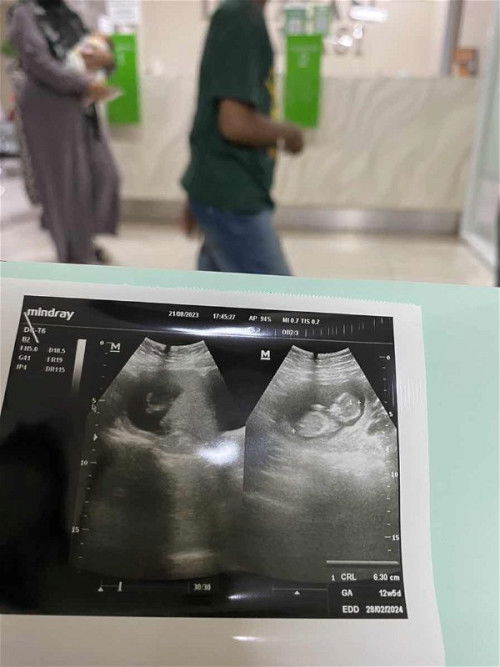

Saya mau tanya Udah masuk 18week knpa ya belum ngerasain gerakan bayi? Padahal hasil usg udah jelas

hamil anak pertama kah Bun,kalo hamil anak pertama wajar biasanya dia sudah gerak di dalem cuma masih halus jadi. bunda blom berasa ,,,kalo anak kedua saya dari 13w sudah merasakan apalagi skarang 18w sudah aktip